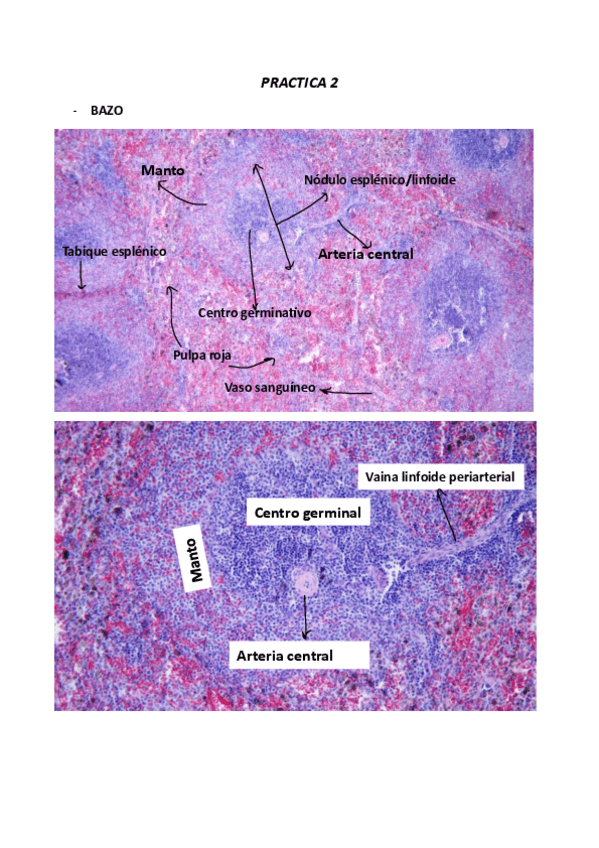

PRACTICAS HISTOLOGIA

PRACTICA-2.pdf